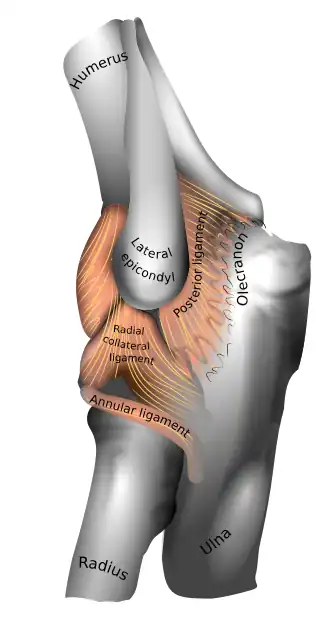

| Left elbow-joint. (Lateral epicondyle visible at center.) | |

Tennis elbow, also known as lateral epicondylitis, is an enthesopathy (attachment point disease) of the origin of the extensor carpi radialis brevis on the lateral epicondyle.[1][5] It causes pain and tenderness over the bony part of the lateral epicondyle. Symptoms range from mild tenderness to severe, persistent pain.[1][6][7] The pain may also extend into the back of the forearm.[3] It usually has a gradual onset, but it can seem sudden and be misinterpreted as an injury.[8][3][9]

The extensor carpi radialis brevis is the most commonly affected muscle in lateral epicondylitis (LE), along with other extensor carpal muscles.[15] Due to its unique origin, the ECRB tendon is prone to abrasion during elbow movements, leading to repetitive microtrauma.